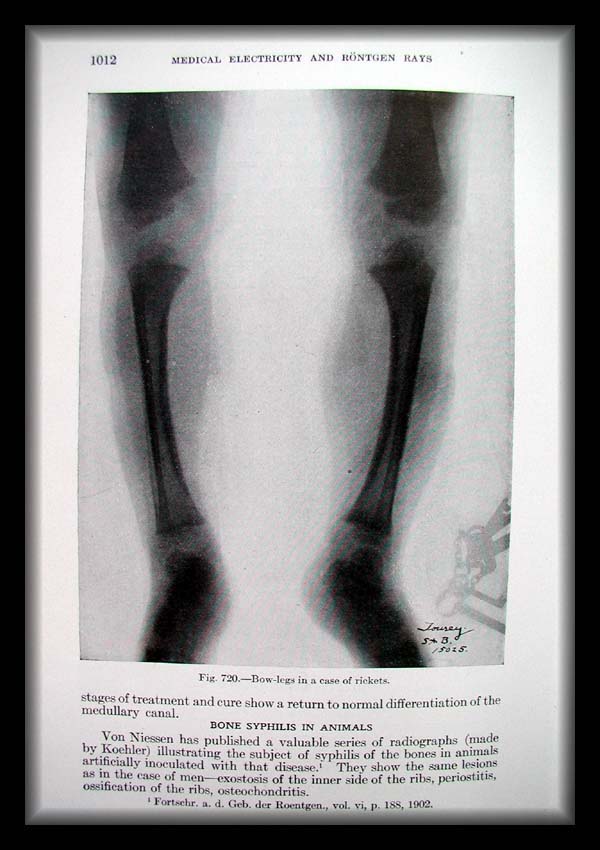

Page1012